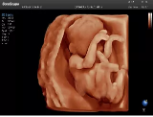

4容積探頭

積探頭是在二維圖像的基礎(chǔ)上,將連續(xù)采集的空間分布位置,經(jīng)過計(jì)算機(jī)重建算法,從而獲得完整的空間形態(tài)。

適用于:胎兒面部、脊柱和肢體等。

優(yōu)勢特點(diǎn):快速獲取、掃查連續(xù)均勻、解剖結(jié)構(gòu)顯示為容積數(shù)據(jù)、準(zhǔn)確進(jìn)行容積測量。